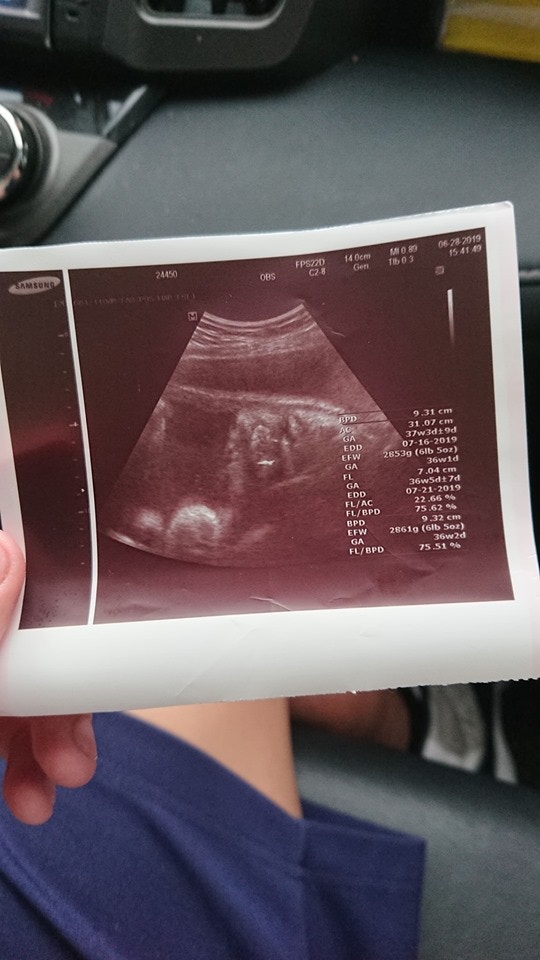

▼於是他們將女方接回家待產,也帶她做了產科產假、超聲波,想不到4天後寶寶就出生了,讓原po超無奈「兒子竟然只給我4天做心理準備!」